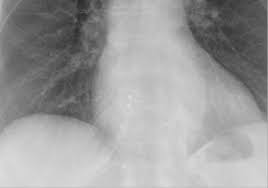

“폐에 물이 찼다”는 말을 들으면 대부분 같은 그림을 떠올리지만, 실제로는 두 가지가 섞여 불리는 경우가 많습니다. 하나는 폐 안(폐포)에 물이 스며드는 폐부종, 다른 하나는 폐 바깥(흉막 사이)에 물이 고이는 흉수(흉막삼출)예요. 둘 다 숨이 차지만, 동반 증상과 위험 신호가 조금 다릅니다. 오늘은 “폐에 물이 차는 증상”을 최대한 쉽게, 실제로 느끼는 증상 중심으로 정리해드릴게요.

폐부종(폐 안에 물)일 때 특징적인 신호

폐부종은 말 그대로 폐포 쪽으로 물이 스며들어 산소 교환이 어려워지는 상태라, 증상이 갑자기 세게 올 수 있습니다. 특히 아래 느낌이 있으면 “그냥 감기인가?”로 넘기기 어렵습니다.

폐부종은 심장 문제(심부전 등)와 함께 오는 경우가 흔해, 갑작스러운 호흡곤란에 가슴 답답함, 식은땀, 심장이 두근거림이 같이 오면 더 주의가 필요합니다.

흉수(폐 바깥에 물)일 때 흔한 느낌

흉수는 폐 바깥쪽 공간에 물이 차서 폐가 눌리는 형태라, 보통은 서서히 숨이 차는 쪽이 많습니다. 초기엔 “체력이 떨어졌나?” 정도로 시작했다가 점점 불편해지기도 해요.